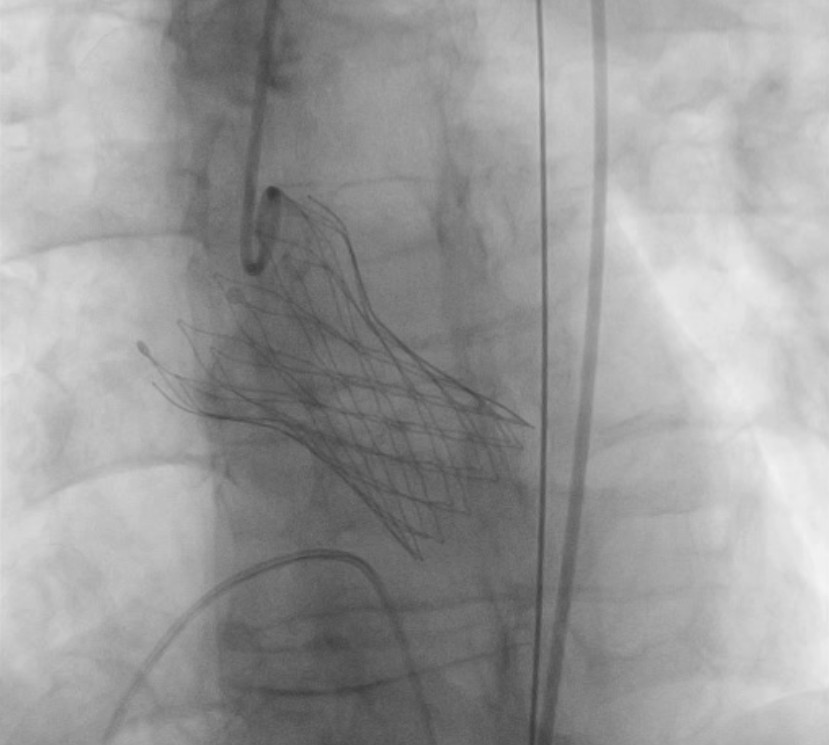

11月12日下午,楚天舒主任团队成功为患者进行了TAVR换瓣治疗,手术中通过导管测量得到植入前心室主动脉压力差大于90mmHg,提示主动脉瓣狭窄已严重阻碍心脏正常泵血工作。人工瓣膜成功植入后,可见人工瓣膜瓣叶开阖自如,心脏对外泵血压力明显减轻,导管测得压力阶差降至10mmHg以下,血流动力学即刻得到改善。这提示着患者的主动脉瓣狭窄情况,已较前大为缓解,手术圆满成功。术后患者生命体征平稳,带气管插管安全返回ICU特护。一天后,患者被转回心血管内科二病区继续治疗。在心血管内科二病区全体医务人员的精心治疗与av线上下,患者于17日顺利出院。